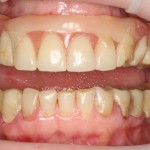

Насколько правдива реклама и отзывы о базальной имплантации? Можно ли им верить? Вот картинки с сайта клиники, которая активно занимается базальной имплантации, я взял одну из их работ. Кому интересно, можно погуглить. Там их очень много, с описанием.

Что отличает все эти демонстрации от того, что мы видим у умных докторов? Ни один из снимков не показывает состояние десны вокруг имплантов (а это, между прочим, является важным критерием качества лечения), все розовое, что вы видите на снимке — это искусственная керамическая или пластмассовая десна. С таким же успехом можно просто удалить пациенту все зубы, поставить съемный протез и сделать фотку. И будет все отлично смотреться. Вот, к примеру, мой пациент, который носит временный съемный протез и готовится к нормальной имплантации:

такой же результат, что и на фотках выше, но без имплантов.